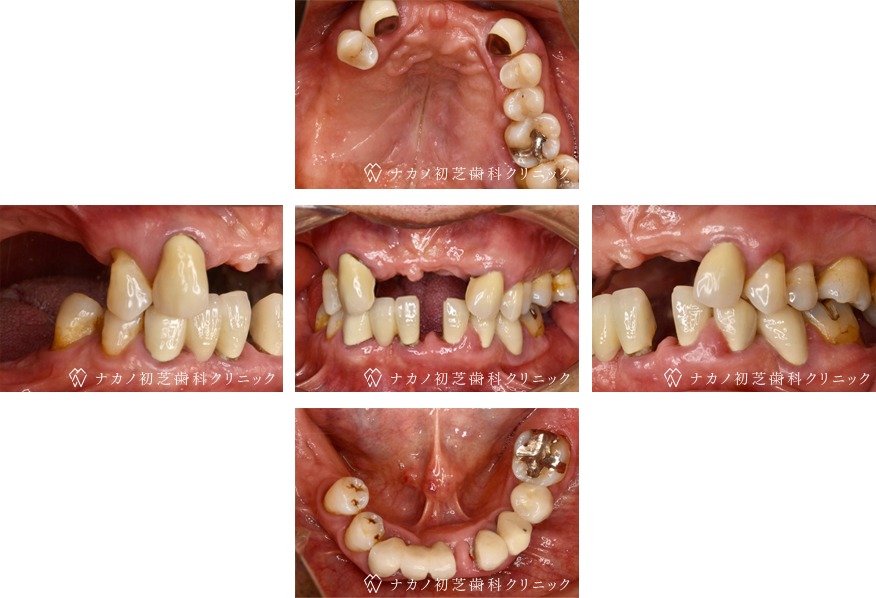

インプラント・13本 (60代女性)

BEFORE

AFTER

年齢 60代女性

治療内容 インプラント治療13本(骨造成の併用)

インプラント治療とは、歯を抜いた所にチタン製の人工歯根を埋入し、その上に歯を入れる方法です。骨を増やすことで、より審美的に治療が出来ました。費用 1本 400,000円(税込 440,000円)

リスク・副作用

腫れ・疼痛・違和感を感じるなどの症状を生じることがあります。